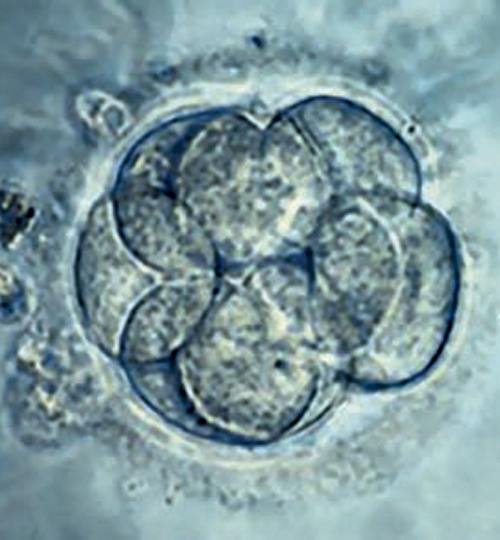

Un lien entre procréation médicalement assistée et risque de cancers chez les enfants nés par ce biais a été évoqué mais reste débattu, faute d’études convaincantes. Pour la première fois, une large étude de cohorte menée à l’échelle nationale à Taiwan, récemment parue dans le JAMA, confirme ce sur-risque, en particulier pour certains cancers…

Des chercheurs à Taiwan ont donc mené une vaste étude de cohorte d’échelle nationale pour déterminer s’il existait une association entre le mode de conception et les cancers de l’enfant, et si cette éventuelle association était médiée ou non par la prématurité et un faible poids de naissance.